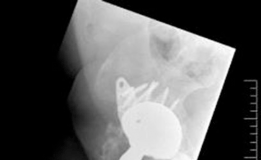

Discover the latest medical recommendations for Solving Severe Acetabular Bone Loss with Cup-Cage Reconstruction. Acetabular bone loss, often due to aseptic loosening of hip implants, manifests as acute groin pain and inability to weight bear. Radiological assessment typically reveals severe osteolysis of the ilium and ischium. Diagnosis centers on the extent of acetabular bone loss. Treatment, such as cup-cage reconstruction, aims to address significant defects and restore stability in complex revision total hip arthroplasty cases.

Meticulous preoperative planning is the cornerstone of successful cup-cage reconstruction. Standard radiography must include an anteroposterior pelvis view, an anteroposterior view of the affected hip, and Judet oblique views (iliac and obturator) to assess the integrity of the anterior and posterior columns. The presence of a pelvic discontinuity is often suggested by a visible fracture line through the acetabulum, medial translation of the inferior hemipelvis, or a break in the Kohler line.

Computed tomography with metal artifact reduction sequence is mandatory. Thin-slice CT allows for precise evaluation of bone stock, the location and size of cavitary and segmental defects, and definitive diagnosis of pelvic discontinuity. Three-dimensional CT reconstructions are increasingly utilized to visualize the defect morphology and aid in the selection of cage size and flange length. In highly complex cases, 3D-printed anatomical models can be sterilized and brought into the operating room for intraoperative contouring of the cage, significantly reducing surgical time.

A highly porous metal cup is then impacted into the defect. The cup is often placed in an off-axis orientation, prioritizing host bone contact and initial stability over anatomic version and inclination. The subsequent cementation of the liner into the cage will correct the final articular geometry. If large cavitary defects remain behind the cup, highly porous metal augments or impacted cancellous allograft are utilized to fill the voids and support the primary shell. Multiple multi-hole screws are placed through the cup into the superior dome and posterior column to maximize initial fixation.